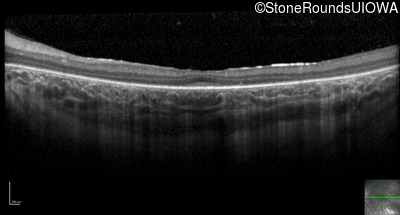

Optical Coherence Tomography - Left - 20/80

Exemplar / OCT Stack

OCT Stack